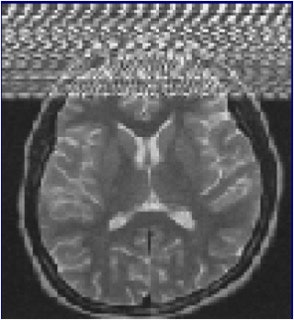

Motion artifacts occur in the phase-encoding axis of the k-space encoding, which usually happens in the vertical axis of the MR image, and this encoding direction of the k-space is considered "slow" and can even take some minutes, they stated in an e-poster at ECR 2015. As the image is being encoded or acquired, motion can occur and different timings are recorded, and hence the final image will not have clear borders and "ghost images" or even spatial blurring occur in the phase-encoding axis of the image.

"Random motion artifacts produce a blurry and noisy image, mainly in the phase-encoding direction, while periodic motion artifacts create ghost images in the phase-encoding direction (e.g., the pulsatility of the arteries, pulsatility artifact)," the authors noted.